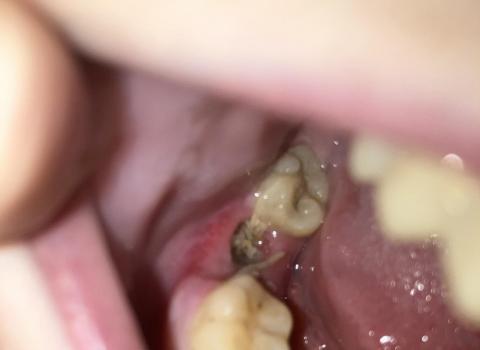

Quick visual impression (from the photo)

-

The socket shows a dark area in the extraction site — that can be a blood clot or residual blood/debris.